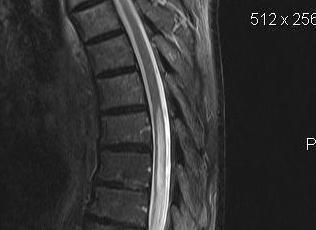

MRI

Most sensitive investigation

- main differential is oedema

- need T1 image

Most common in lower C Spine

- may progressively extend up to medulla & down to lumbar

- fluid-filled tubular cavity

- separate from but usually communicating with central canal

2. Lumbar

- dissociate lumbosacral sensory loss

- weakness & wasting of legs & pelvic girdle

- diminished reflexes / Babinski negative

- impaired bowel & bladder function